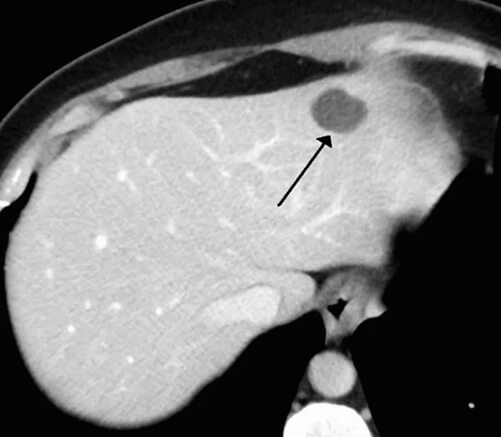

4. 간 혈관종을 진단하려면?

간 혈관종을 진단하기 위해서는 다양한 방법을 사용할 수 있습니다. 여기서 잘 알고 가야 할 것이 한 가지 있습니다. 먼저 간 혈관종이 의심되는 사람이 평소 간이 건강한 사람인지, 아니면 간질환이나 간암을 앓았던 환자인지를 파악해야 합니다.

만약 평소 간에 아무 문제가 없는 환자라면 영상 검사로도 충분히 혈관종이라는 것을 판단할 수 있습니다. 하지만 만성 간 질환이나 간암이 걸렸던 적이 있는 환자들은 간 혈관종처럼 보이는 악성 종양일 수도 있기 때문에 영상학적인 진단 말고 다른 검사들을 통해 정확하게 진단을 받아야 합니다.

간 혈관종을 검사하기 위해서 진행하는 방법은 혈관 조영 검사/테크네슘-적혈구 스캔 검사/복부 MRI/복부 CT 등이 있습니다. 급여가 안되는 검사는 진단비가 많이 비싸기 때문에 지원받을 수 있는 것들을 미리 알아보셔야 합니다.